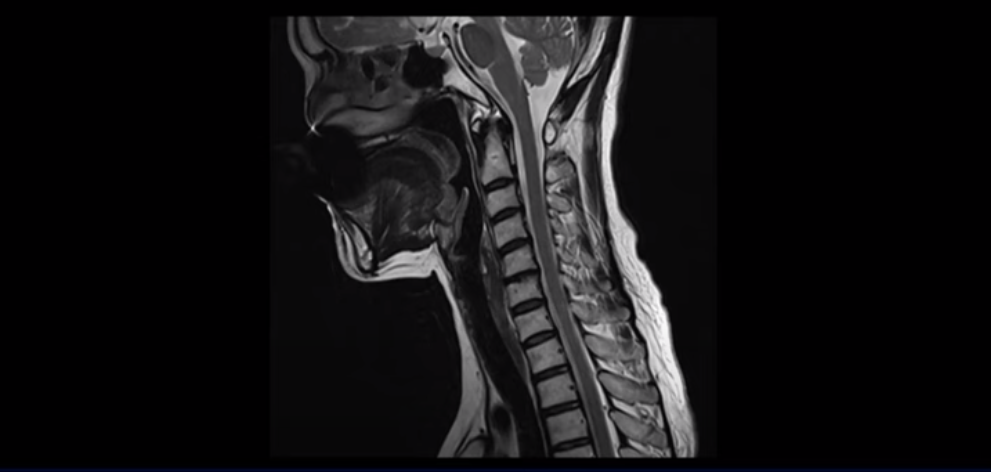

이분 MRI를 보실까요? 일자목에 머리가 앞으로 밀려 나간 거북목 체형입니다.

50대 후반에 근육이 많이 줄어들고 약해진 여성 환자들에게서 많이 보이는 체형입니다. 거북목에 등은 굽어있고 어깨도 앞으로 말려 있으면 등 근육과 뒷목 근육이 머리를 붙잡고 있느라 긴장되고 뭉치고 아플 수밖에 없습니다. 게다가 이분 근육을 검사했더니 놀랍게도 근감소증이 나왔습니다. 근육량도 기준보다 훨씬 더 적은 겁니다. 그러니까 다른 환자들보다도 더 심하게 아프고 오랫동안 아플 수밖에 없는 겁니다.

이렇게 줄어들고 약해진 근육으로 거북목과 등이 굽은 자세를 장시간 유지하면서 무리한 일을 하면, 등이나 목이 심하게 아플 수밖에 없습니다. 이분은 쌍둥이 손주들을 봐주면서 등 통증이 시작됐다고 하셨는데요. 그런데 이 아픈 등 근육만 치료하면 단기적으로 며칠간은 안 아플지 몰라도 결국은 이 자세를 교정하고 몸 앞쪽 근육들을 치료하지 않으면 근본적인 치료가 될 수가 없습니다.